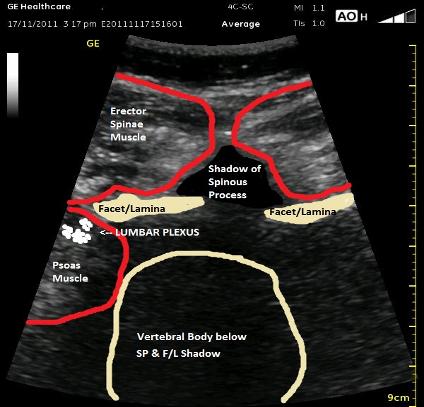

The ultrasound picture below is a midline transverse view between the Transverse Processes which will allow an out of plane or in plane (medial or lateral) needle approach. For any of these approach, it would be helpful to slide the probe laterally a few centimeters. Notice that the Lumbar Plexus estimation is in the posterior 1/3 of the Psoas Muscle belly. The Spinous Process does reach superficially because the beam is not crossing at its highest point. The Vertebral Body is likely larger than what is represented in the cartoon image, and the medial border of the Psoas Muscle is also estimated due to the bone shadow from the Lamina/Facet above.